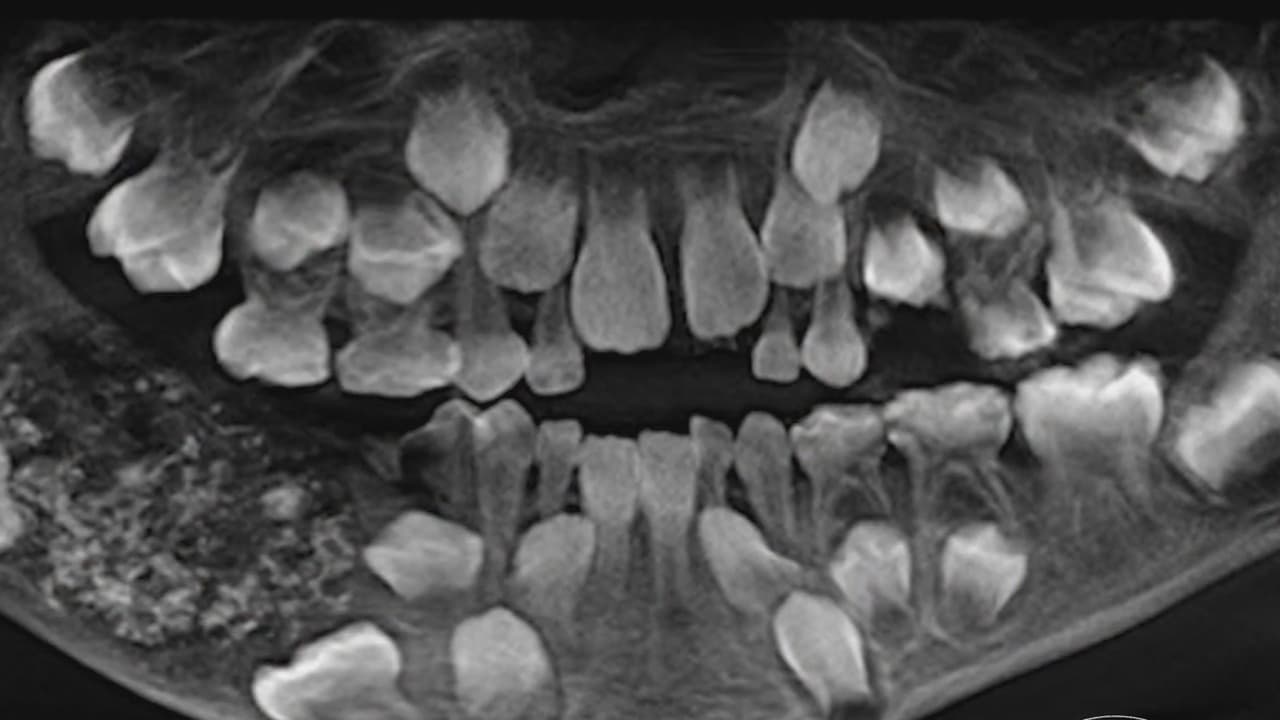

Un niño de 7 años con 526 dientes fue lo que reveló una radiografía: entérate cómo terminó este insólito caso

Un pequeño de esa edad tiene normalmente 20 dientes, que pasan a ser 32 cuando es adulto. Pues este menor en India tenía más de 500, por lo que requirió cinco horas de cirugía pare remover los cientos de piezas dentales sobrantes, en un caso único en el mundo.